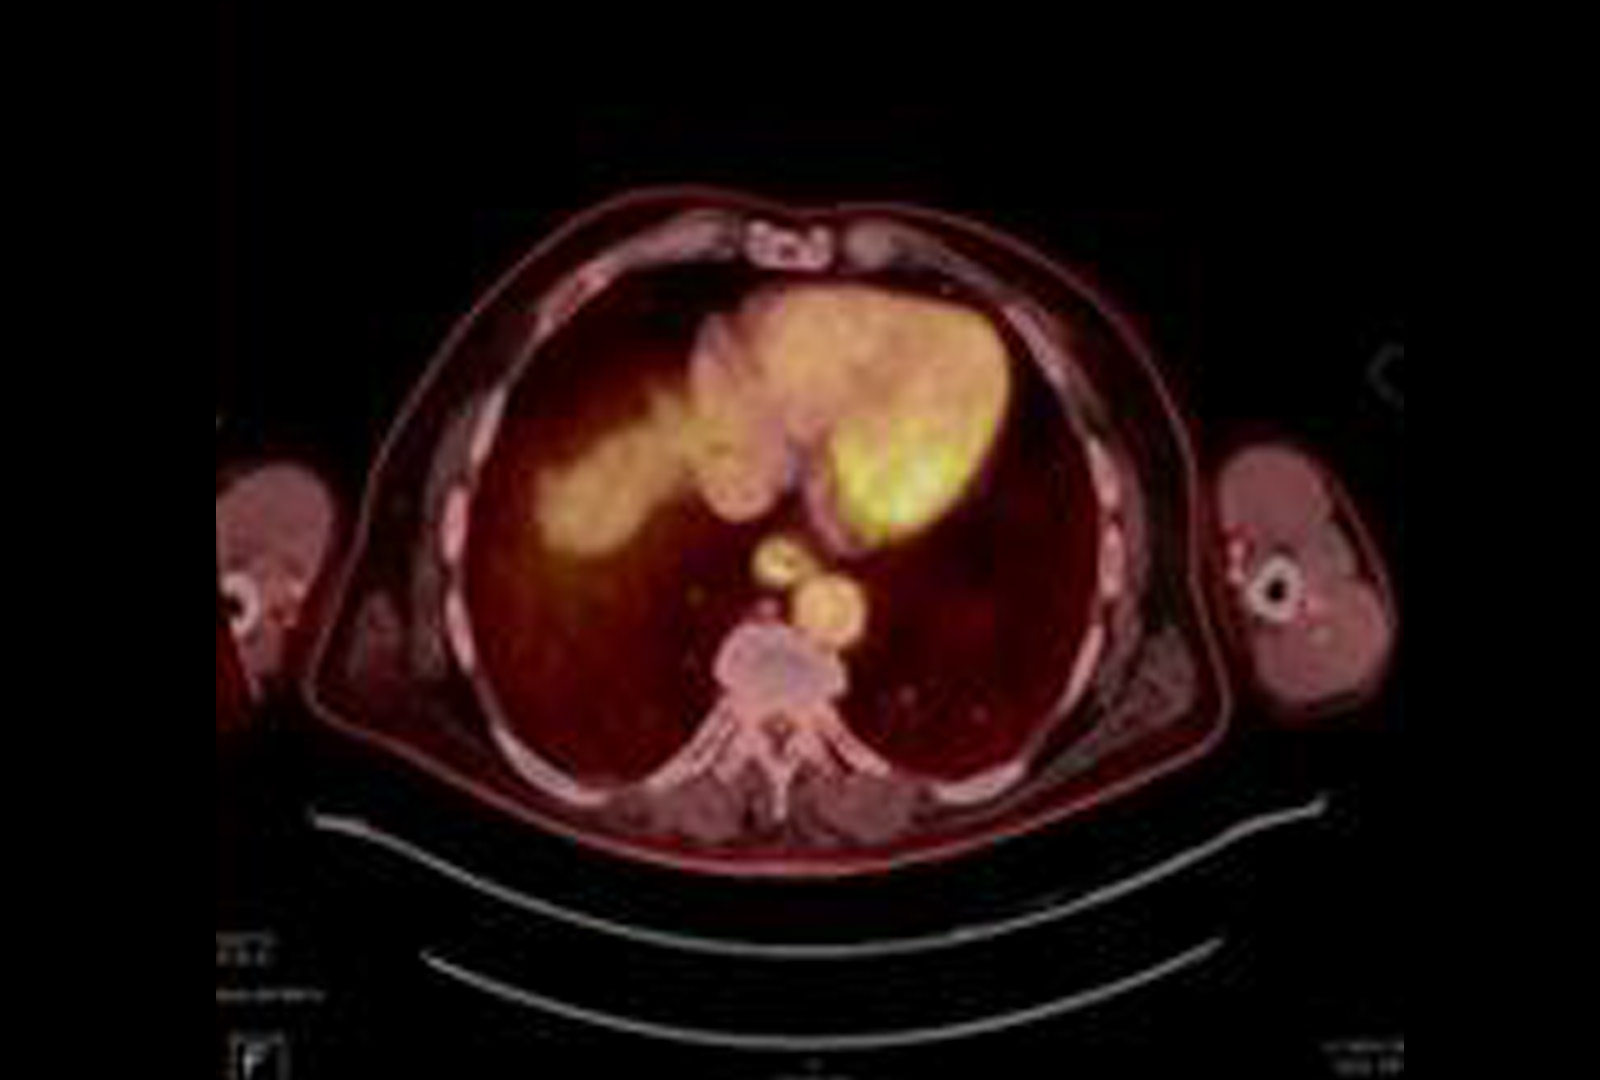

FDG Uptake

PET/CT showing FDG uptake at the distal esophagus, consistent with malignancy. There is also FDG uptake at the gastroesophageal junction, likely inflammatory or physiologic, along with FDG-avid bilateral hilar foci, right axillary nodes, and a right inguinal node—findings most consistent with inflammation. Source: NYU Langone Health